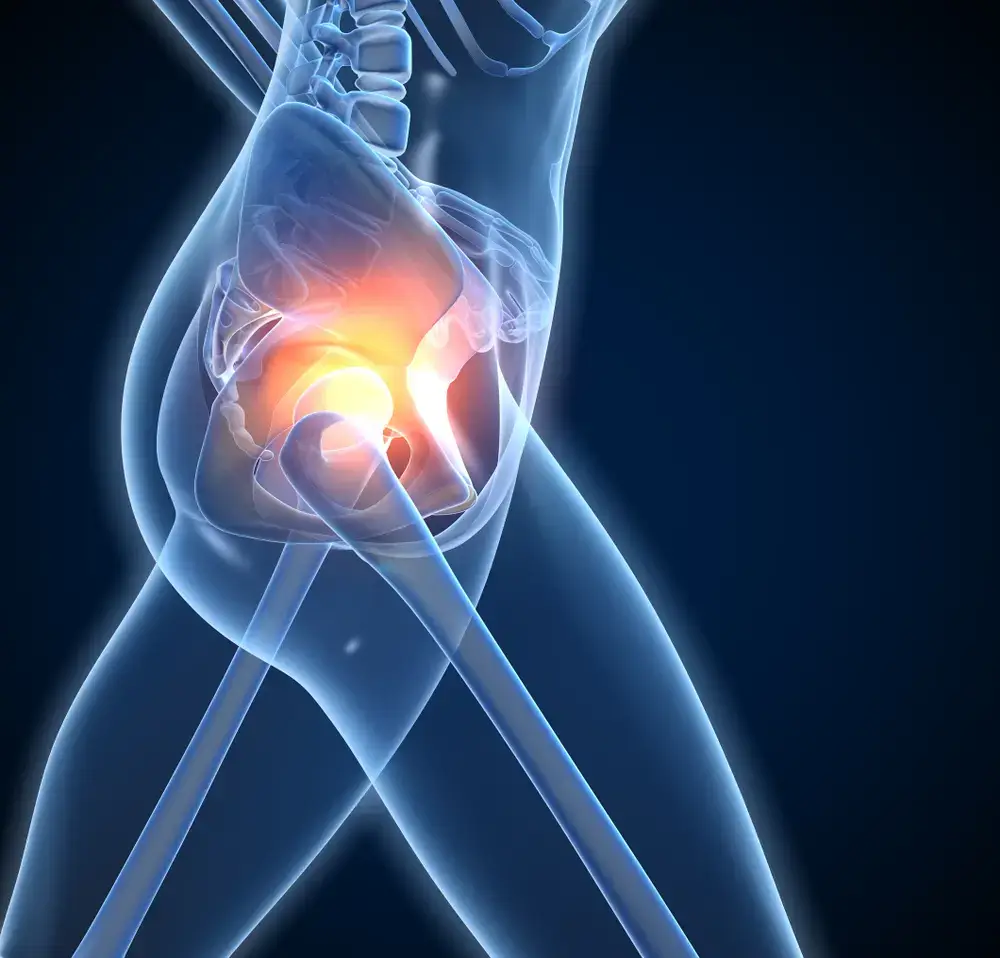

JOINTS PAIN ISSUES

Joints are the areas of the body where two bones meet. There are many different joints in the body, and each one has a specific job. The hip joint is a ball-and-socket joint. This type of joint allows for a great range of motion. The hip joint is important for activities such as walking, running, and jumping.

Joints Issues can cause hip pain. Osteoarthritis, the most common type of arthritis, is a degenerative joint disease that affects the cartilage and bones in your joints. It can occur in any joint in your body but is most common in the hands, knees, and hips. Symptoms of osteoarthritis include stiffness, swelling, and pain.

HOW OSTEOPATHY FOR HIP AND JOINT PAIN CAN HELP?

Osteopathy may have a substantial impact on the treatment and management of your hip pain, but this is dependent on the source of the pain and the extent of the damage already done. To identify the best course of treatment, our osteopathic practitioner in Stoney Creek will look at the patient as a whole rather than simply the symptoms. The key to osteopathy therapy is to gently move the hip joint to stretch the soft tissues and disseminate synovial fluid (the joint’s natural lubrication) throughout the whole joint surface. In this case, your osteopath may use trigger point, fascia, visceral, or craniosacral treatment. One study found that osteopathy was effective for treating hip pain in both children and adults. Participants who received osteopathic treatment reported significant reductions in pain and improvements in function. Another study showed that osteopathy was more effective than physical therapy for treating hip impingement syndrome.